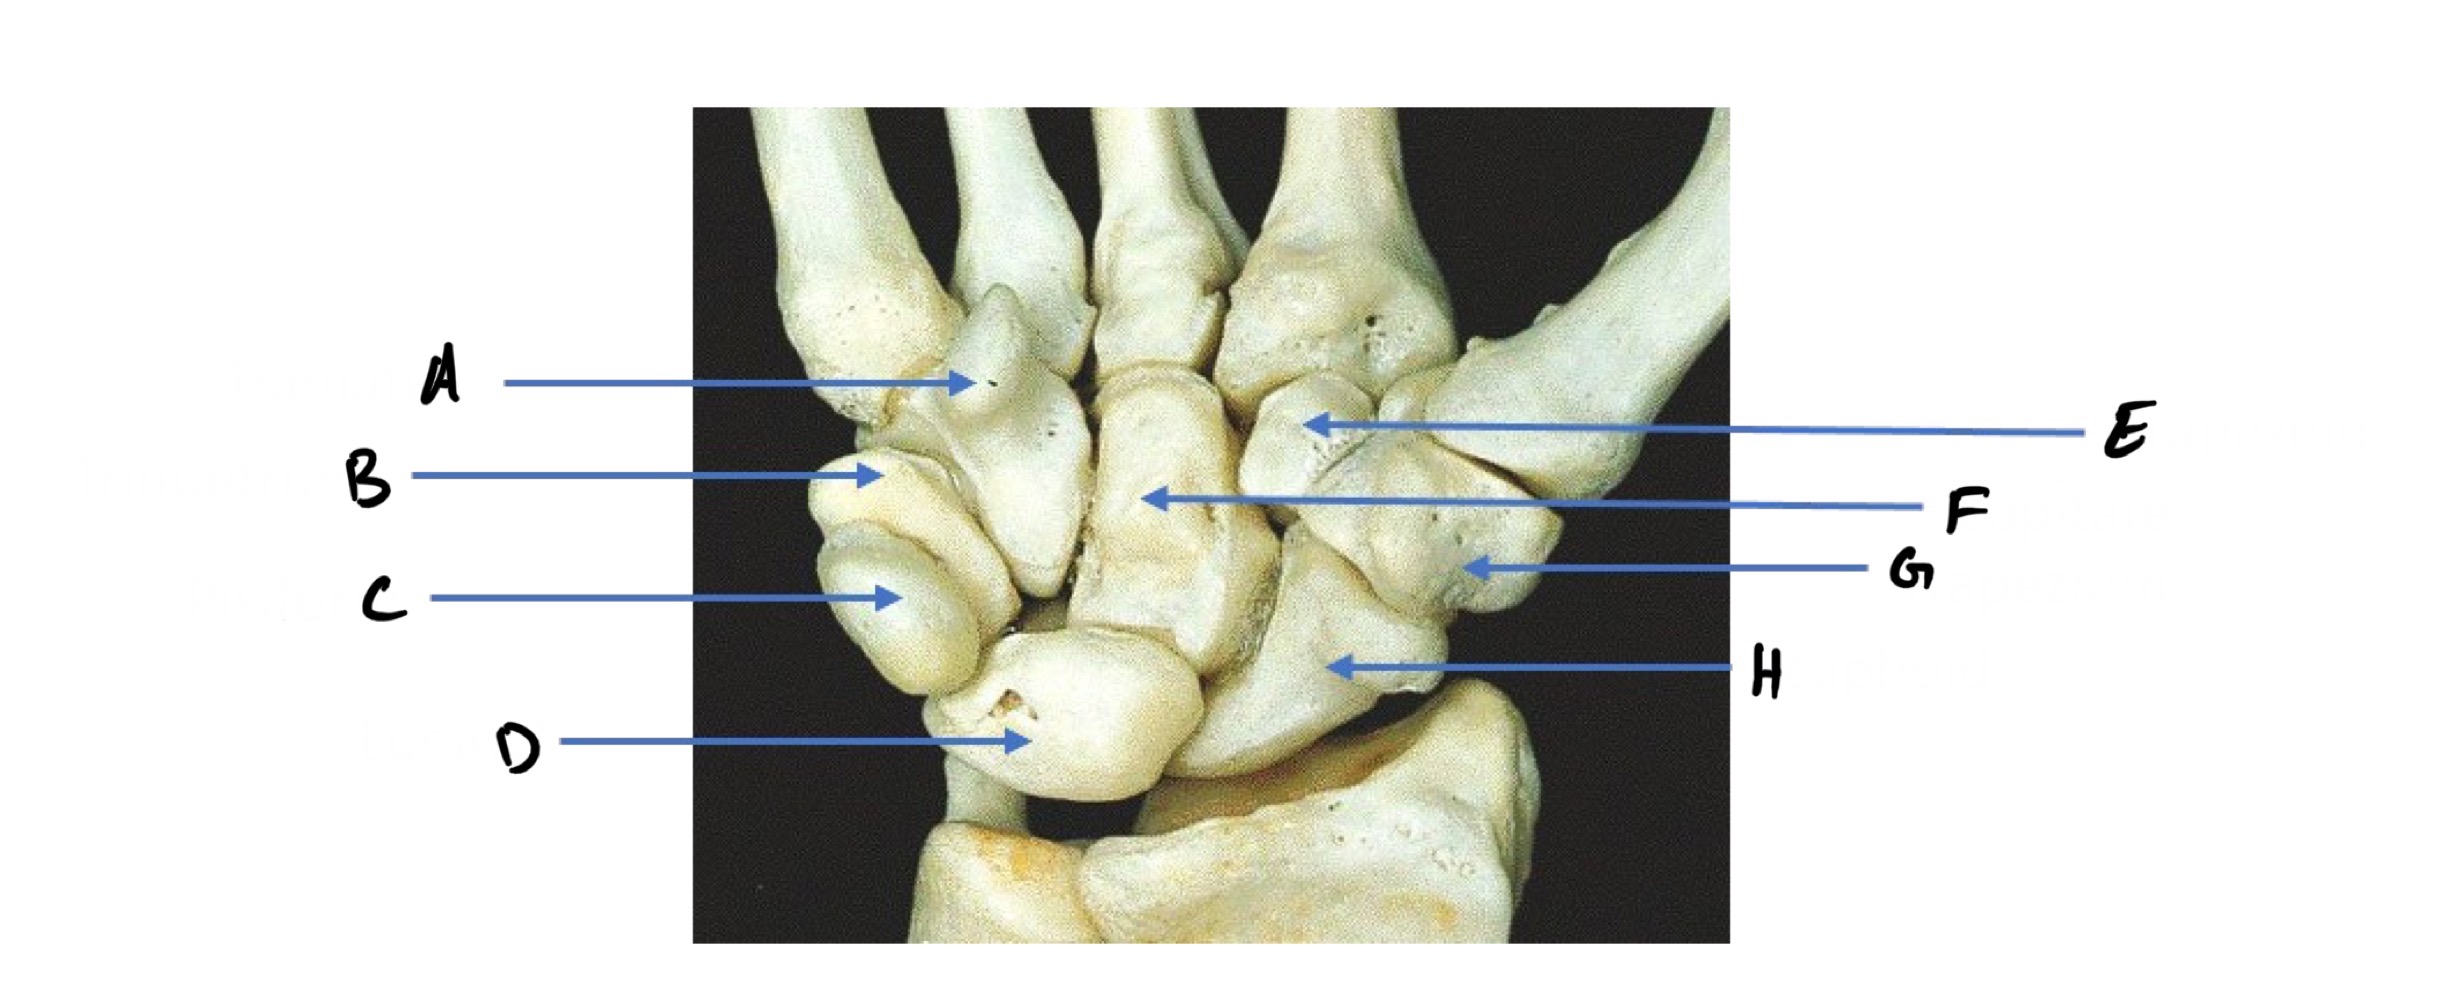

A

Hamate (Hammer shape)

B

Triquetrum

C

Pisiform (pea shape)

D

Lunate (like moon shape - lunar)

E

Trapezoid

F

Capitate (captain - biggest carpal bone)

G

Trapezium

H

Scaphoid